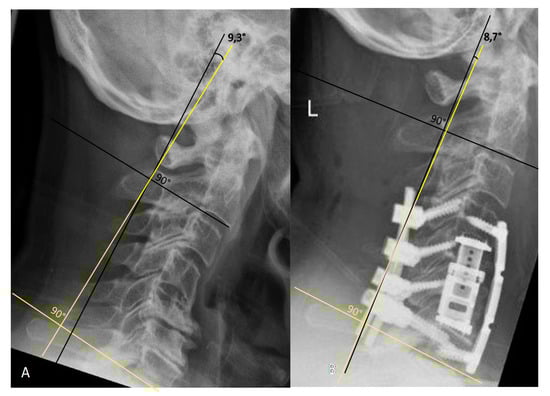

3.2. Radiological Outcome